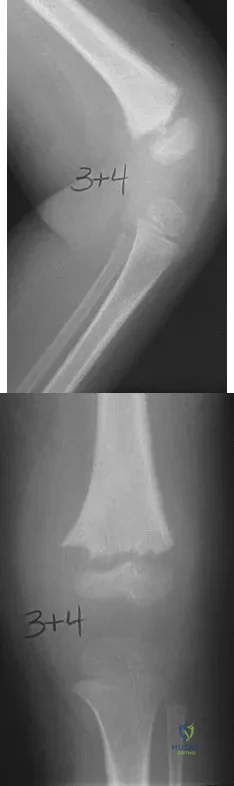

Question 3High Yield

A 25-year-old professional baseball pitcher reports a 4-month history of gradually increasing medial elbow pain that occurs during the late cocking and acceleration phases of throwing. The pain occasionally refers distally along the ulnar aspect of the forearm. He denies any weakness; however, he notes occasional paresthesias. A nerve conduction velocity study demonstrates increased latency across the cubital tunnel. Management consisting of 6 weeks of rest and rehabilitation fails to provide relief as the symptoms returned when he resumed throwing. What is the best course of action?

In the thrower's elbow, ulnar neuritis is felt to result from both chronic compression and traction on the nerve that occurs during the throwing motion. Occasionally, subluxation of the nerve also can lead to symptoms. If nonsurgical management fails to provide relief, transposition of the nerve to an anterior subcutaneous location is the surgical procedure of choice. The nerve is held in its new position by one or two fascial slings created from the fascia of the common flexor origin. Schickendantz MS: Diagnosis and treatment of elbow disorders in the overhead athlete. Hand Clin 2002;18:65-75.